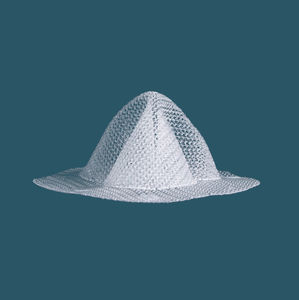

- Prothese für Nabelhernie

Prothese für Nabelhernie

... Implantierbares Mesh-Gerät zur Wandverstärkung und lang anhaltenden Stabilisierung. CRISTALENE bietet - Weitporiges Netz, das das Infektionsrisiko reduziert - Polypropylen-Monofilamente, die eine gute Gewebeintegration ermöglichen und ...

Doppelseitige Parietalprothese mitExpansionsballon (je nach Referenz). Gewebeunterstützung und Stärkung von Nabel- oder Narbenhernien. Intraperitoneale Implantation. Technische Daten Zusammensetzung Eine Seite aus monofilament ...

... Einzigartiges dreidimensionales Polypropylennetz für die laparoskopische Hernienreparatur. Spannungsfreie Hernienreparatur Minimale Invasion Weniger abgetrenntes Gewebe Weniger Schmerzen nach der Operation Schnellere Genesung ...